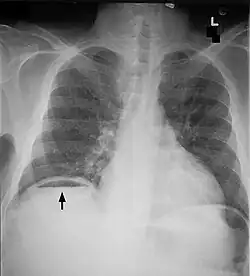

Bowel obstructions are commonly secondary to adhesions, hernias, or cancer. Bowel obstruction can be an emergency requiring immediate surgery. Original testing and imaging include blood tests for electrolyte levels, and abdominal X-rays or CT scans. Treatment often begins with IV fluids to correct electrolyte imbalances. Obstructions may be complicated by ischemia or perforation of the bowel. These cases are surgical emergencies and often require bowel resection to remove the cause of obstruction.[13] Adhesions are a common causes of obstruction, and frequently resolve without surgery.[14]

Bowel perforation presents with abdominal pain, free air in the abdomen on standing X-ray, and sepsis.[15][16][17] Depending on the cause and size, perforations may be medically or surgically managed. Some common causes of perforation are cancer, diverticulitis, and peptic ulcer disease.